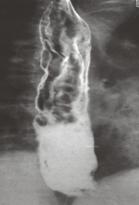

identificarea varicelor se face prin examen radiologic cu pasta groasa baritata

- examen radiologic cu pasta baritata;